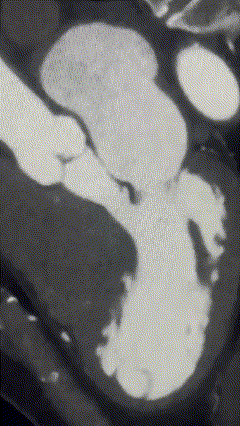

Imagem da Semana

E essa cardiopatia hipertrófica obstrutiva com movimento de SAM da valva mitral vista à angiotomografia? Esse paciente estava em programação de realização de ablação do septo por radiofrequência.

Mais bonita que essa imagem, só a edição da DozeNews Prime na qual discutimos as nuances do tratamento da CMH.